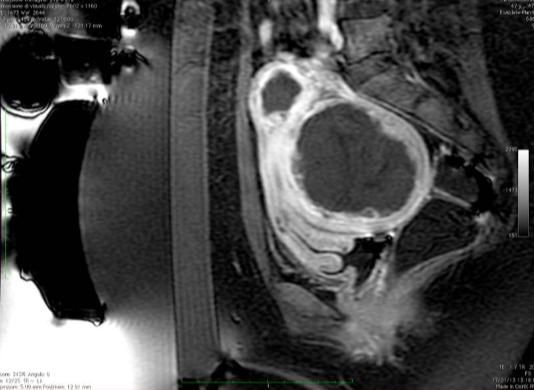

28 岁女性,下腹部疼痛及腹部紧张症状

![]() |

| 治疗前后对比 |